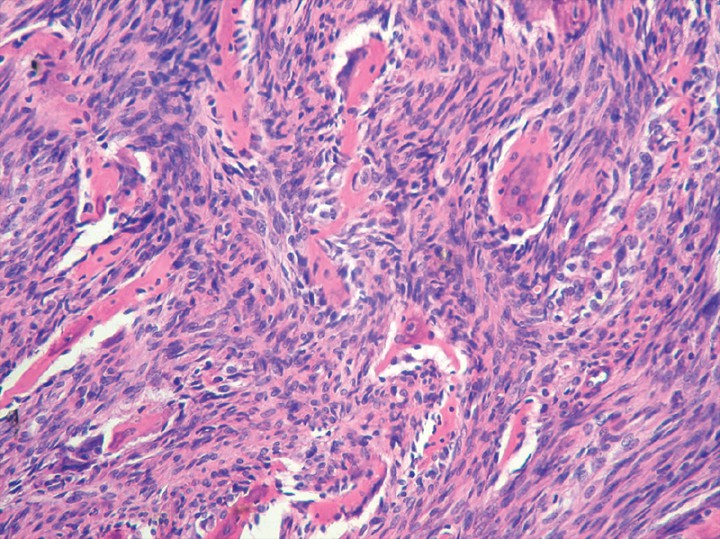

Se realizó estudio anatomopatológico de varias muestras de la pieza anatómica extirpada, diagnosticándose osteosarcoma osteoblástico de bajo grado histológico.[ Craig LE, Dittmer KE, Thompson KG: Bones and joints, en Maxie MG (ed) Jubb, Kennedy & Palmer’s Pathology of Domestic Animals. 6ª ed. St Louis: Elsevier, 2016; 110-115. , Selmic LE, Lafferty MH, Kamstock DA, Garner A, Worley DR, Withrow SJ, el al. Outcome and pronostic factors for osteosarcoma of the maxila, mandibule or calvarium in dogs: 183 cases (1986-2012). J Am Vet Med Assoc. 2014; 245: 930-938. [PubMed] ] Las muestras remitidas presentaban áreas de proliferación neoplásica mesenquimatosa, formadas por elementos de rasgos fusiformes y pleomórficos que, con un bajo índice mitótico, progresaban mostrando una marcada actividad osteosintética y generando escasa necrosis (Fig. 6).

<p>Imagen microscópica del tejido extirpado. Se observan áreas de proliferación neoplásica mesenquimatosa formadas por elementos de rasgos fusiformes y pleomórficos con bajo índice mitótico (Hematoxilina & Eosina x 200). Diagnóstico: osteosarcoma osteoblástico de bajo grado (imagen cedida por Histovet).</p>

Imagen microscópica del tejido extirpado. Se observan áreas de proliferación neoplásica mesenquimatosa formadas por elementos de rasgos fusiformes y pleomórficos con bajo índice mitótico (Hematoxilina & Eosina x 200). Diagnóstico: osteosarcoma osteoblástico de bajo grado (imagen cedida por Histovet).